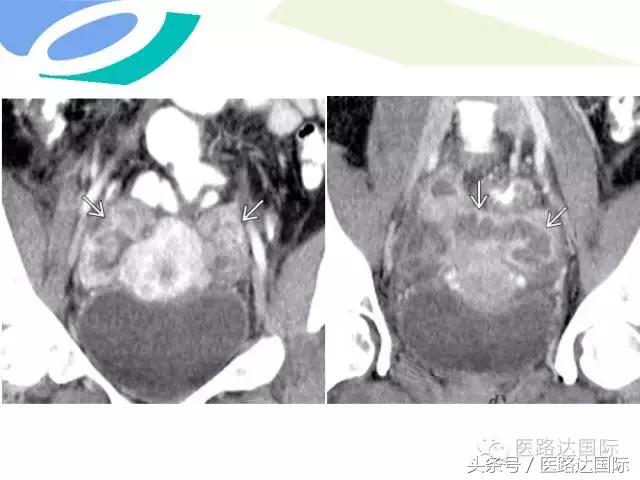

首都医科大学附属北京妇产医院梁宇霆教授从流行病学、临床特点、实验室检查、病理改变、影像学特点及治疗与预后六个方面向我们详细地介绍了女性生殖系统结核;并且着重介绍了子宫输卵管造影(HSG)的作用。在最后,梁教授还向大家介绍了如何鉴别诊断女性生殖系统结核、盆腔炎性病变和卵巢癌。

女性生殖系统结核的影像诊断及鉴别